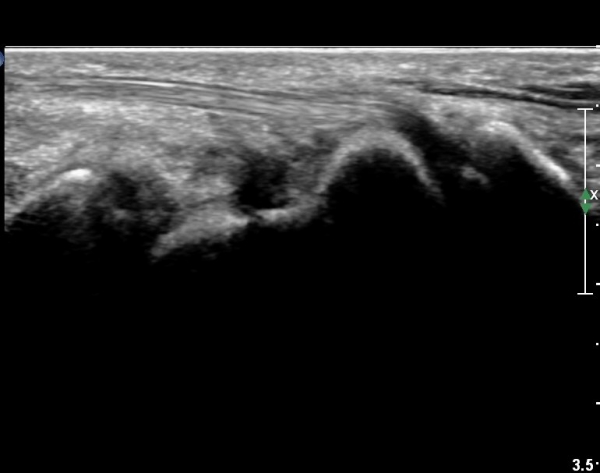

¼Õ¸ñ ¿ä°ñÃø ÁÖ»ó°ñ Á¾´Ü¸é °Ë»ç¿¡¼ ÁÖ»ó°ñ ÇÇÁú°ñ ¿¬¼Ó¼º ¼Ò½ÇÀÌ ¶Ñ·ÈÇÏ°í µ¿¹ÝµÈ ¿¬ºÎÁ¶Á÷ ºÎÁ¾ÀÌ °üÂûµÊ(»çÁø 3, 4)/

È®ÁøÀ» À§ÇÑ ÃÊÀ½ÆÄ°Ë»ç¿¡¼ ÁÖ»ó°ñ °ñÀý È®ÀÓ µÊ.